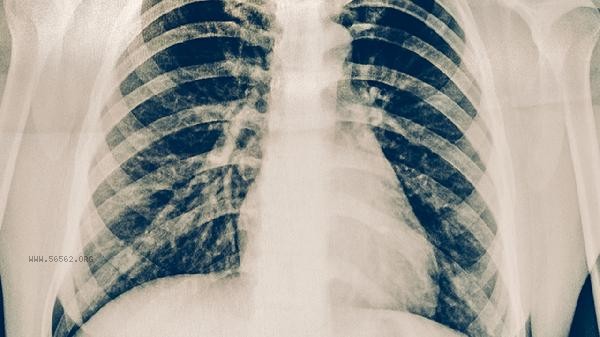

Abnormal sub items of lung volume may indicate different diseases, such as increased residual gas volume commonly seen in emphysema. Abnormal total lung volume reflects overall lung function impairment, and the combination of the two can more accurately determine obstructive or restrictive lung diseases.

Lung volume is measured in segments using a pulmonary function meter, and specific respiratory movements are required. The total lung volume is often measured using gas dilution method or physical box method, and the data from both methods need to be cross validated to improve accuracy.